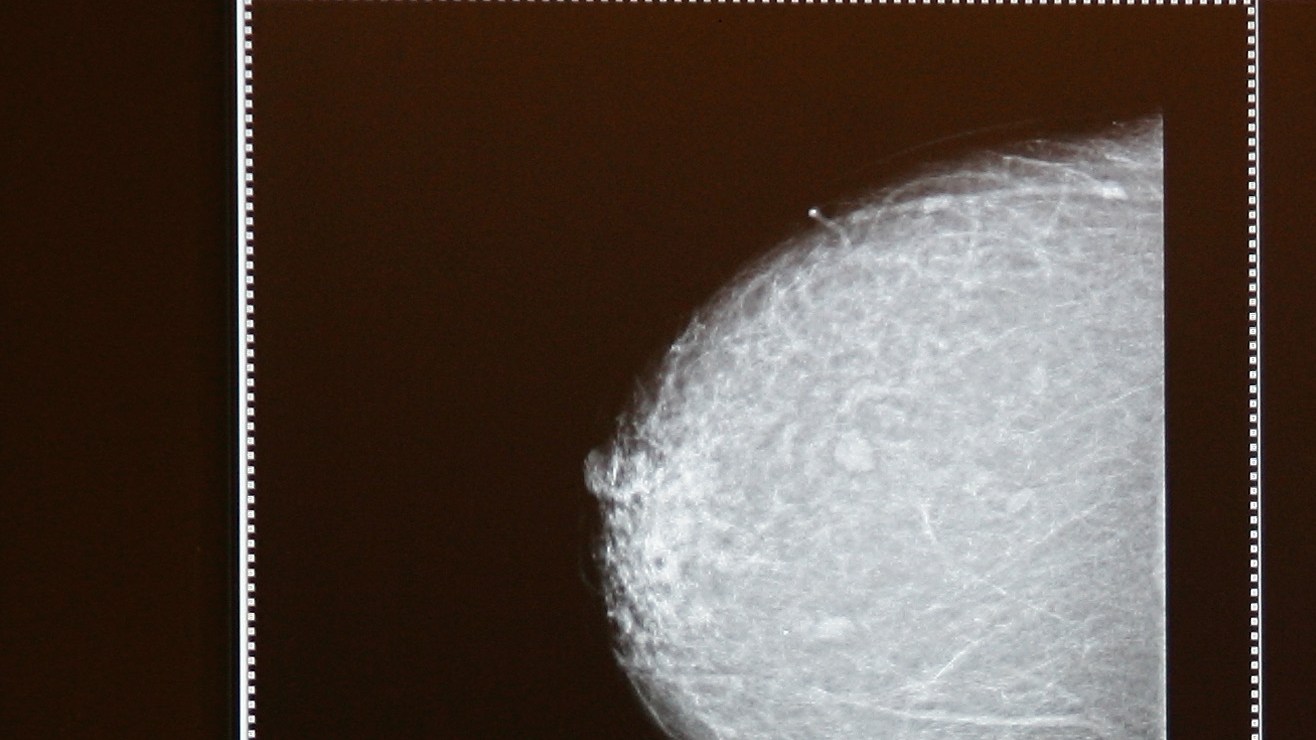

Imágenes digitales de un estudio de mamografía, técnica usada para detectar cáncer de mama. Crédito: Getty Images